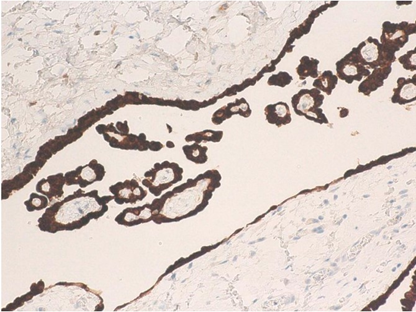

Microscopic examination showed that a papillary pattern accompanied by a glandular pattern, and the papillary areas were lined by a single cuboidal mesothelial cells (Figure 3), with one case (Figure 4, Case 8), having a mild nuclear atypia. In general, the mesothelial cells lacked mitotic activity. In addition, less than 1% of cells were positive for MIB-1 antibody (Figure 5). Immunohistologic studies showed a positive calretinine, CK7 (Figure 6) and D2-40 (Figure 7) and a negative CEA. In case 8, submesothelial invasive tumor of higher cytologic grade was detected in one of 23 sections from resected specimen.

Figure 5: Immunohidtochemical findings by Ki-67 antibody (Case 8: left, and Case 1: right).

Figure 6: CK7 immunoreaction in case 4.